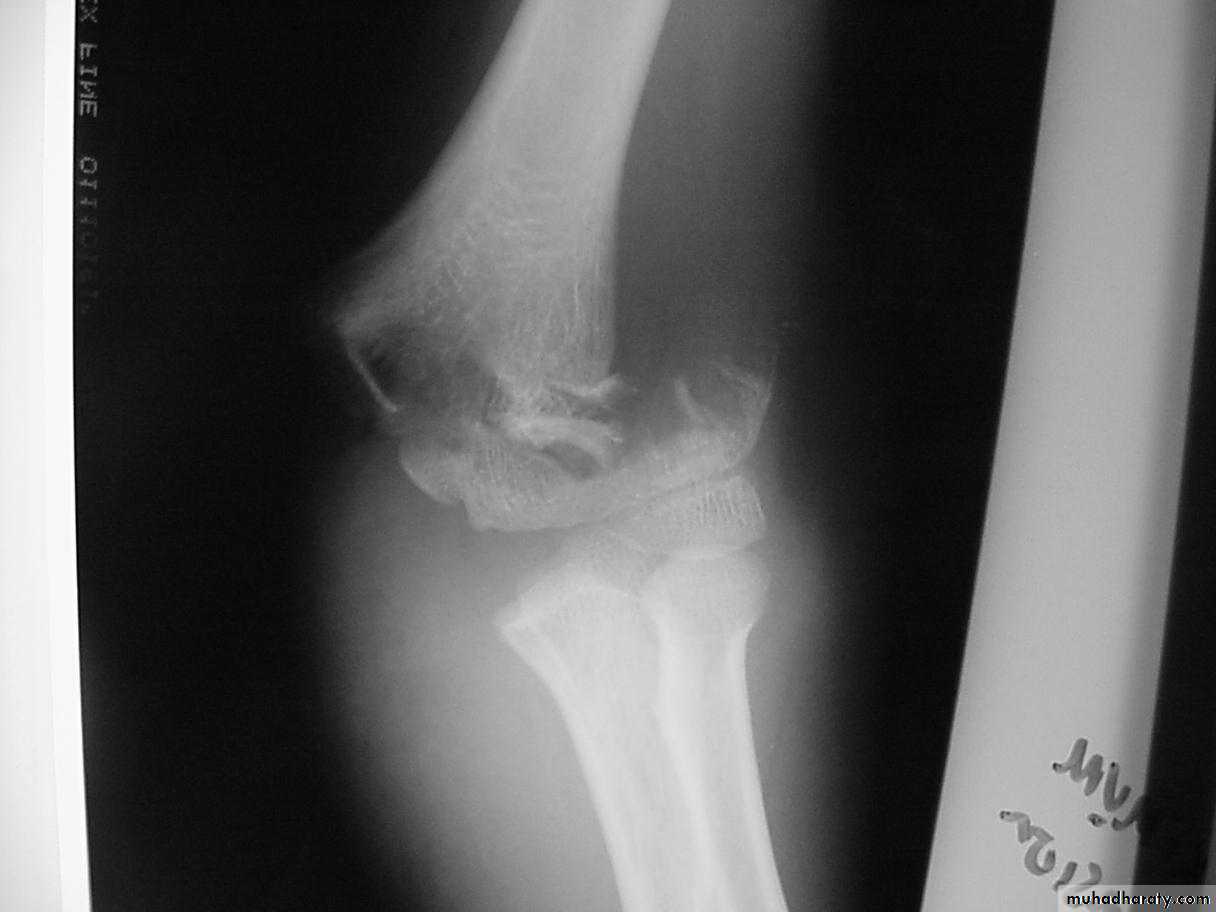

2. The distal fragment is in valgus.

3. The medial spike of the proximal fragment is usually posterior.

Posteromedial vs. Posterolateral

The rate of complications is greater with the posterolateral fractures.

with the posteromedial fractures ?The radial nerve

is more vulnerableto injury.